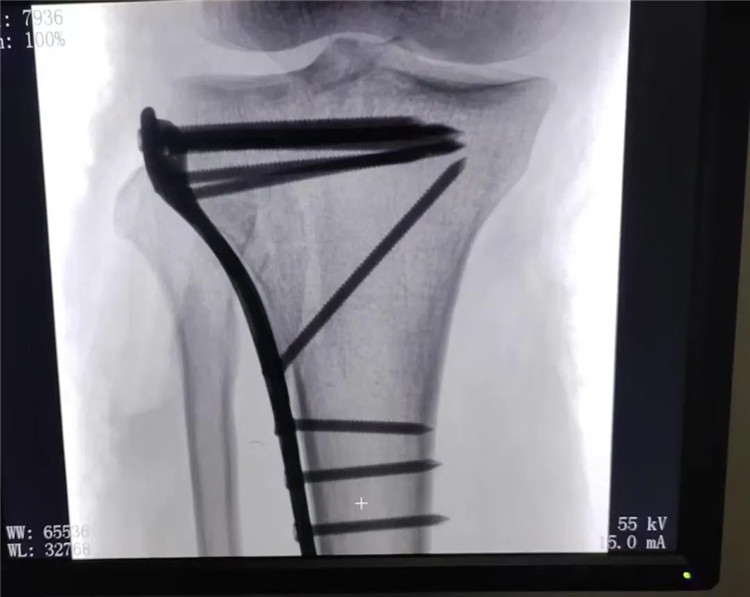

术前膝关节DR及CT影像提示胫骨外侧平台粉碎塌陷骨折并关节腔游离骨折块